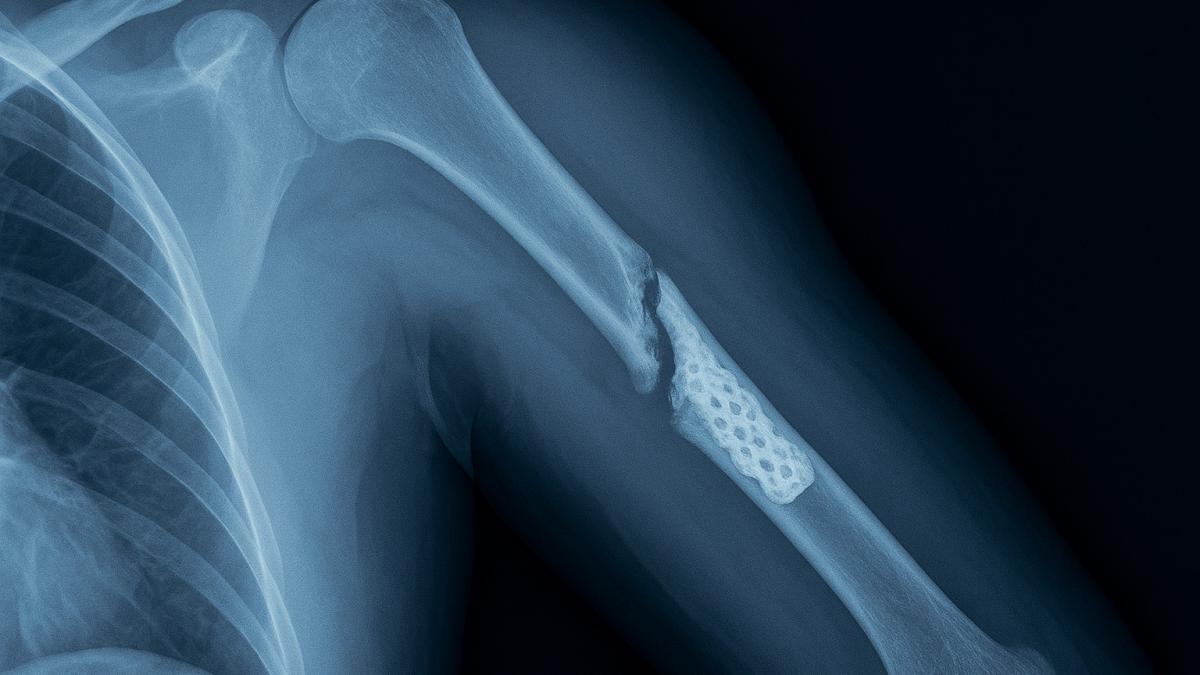

Зима приносит не только красоту, но и опасность — лёд под ногами становится причиной множества травм. В гололёд достаточно одного неловкого шага, чтобы оказаться на земле. По словам хирурга Игоря Клочихина, чаще всего при падении страдают шейка бедра и лучевая кость — это тяжёлые переломы, требующие длительного восстановления. Однако многие повреждения можно предотвратить или облегчить, если знать, как правильно действовать.

"Наиболее распространённые травмы при падении на льду — это переломы шейки бедра и лучевой кости. Они часто вызывают ограничение подвижности и серьёзные осложнения", — отметил хирург Игорь Клочихин.

Даже если кажется, что травма лёгкая, осмотр специалиста необходим. Некоторые переломы, особенно трещины костей или разрывы связок, проявляются не сразу.

Пожилым людям особенно важно не пытаться встать самостоятельно. Лучше вызвать скорую помощь, даже если боль кажется умеренной. У них часто происходят скрытые переломы шейки бедра, которые не сразу проявляются болью, но могут привести к инвалидности.